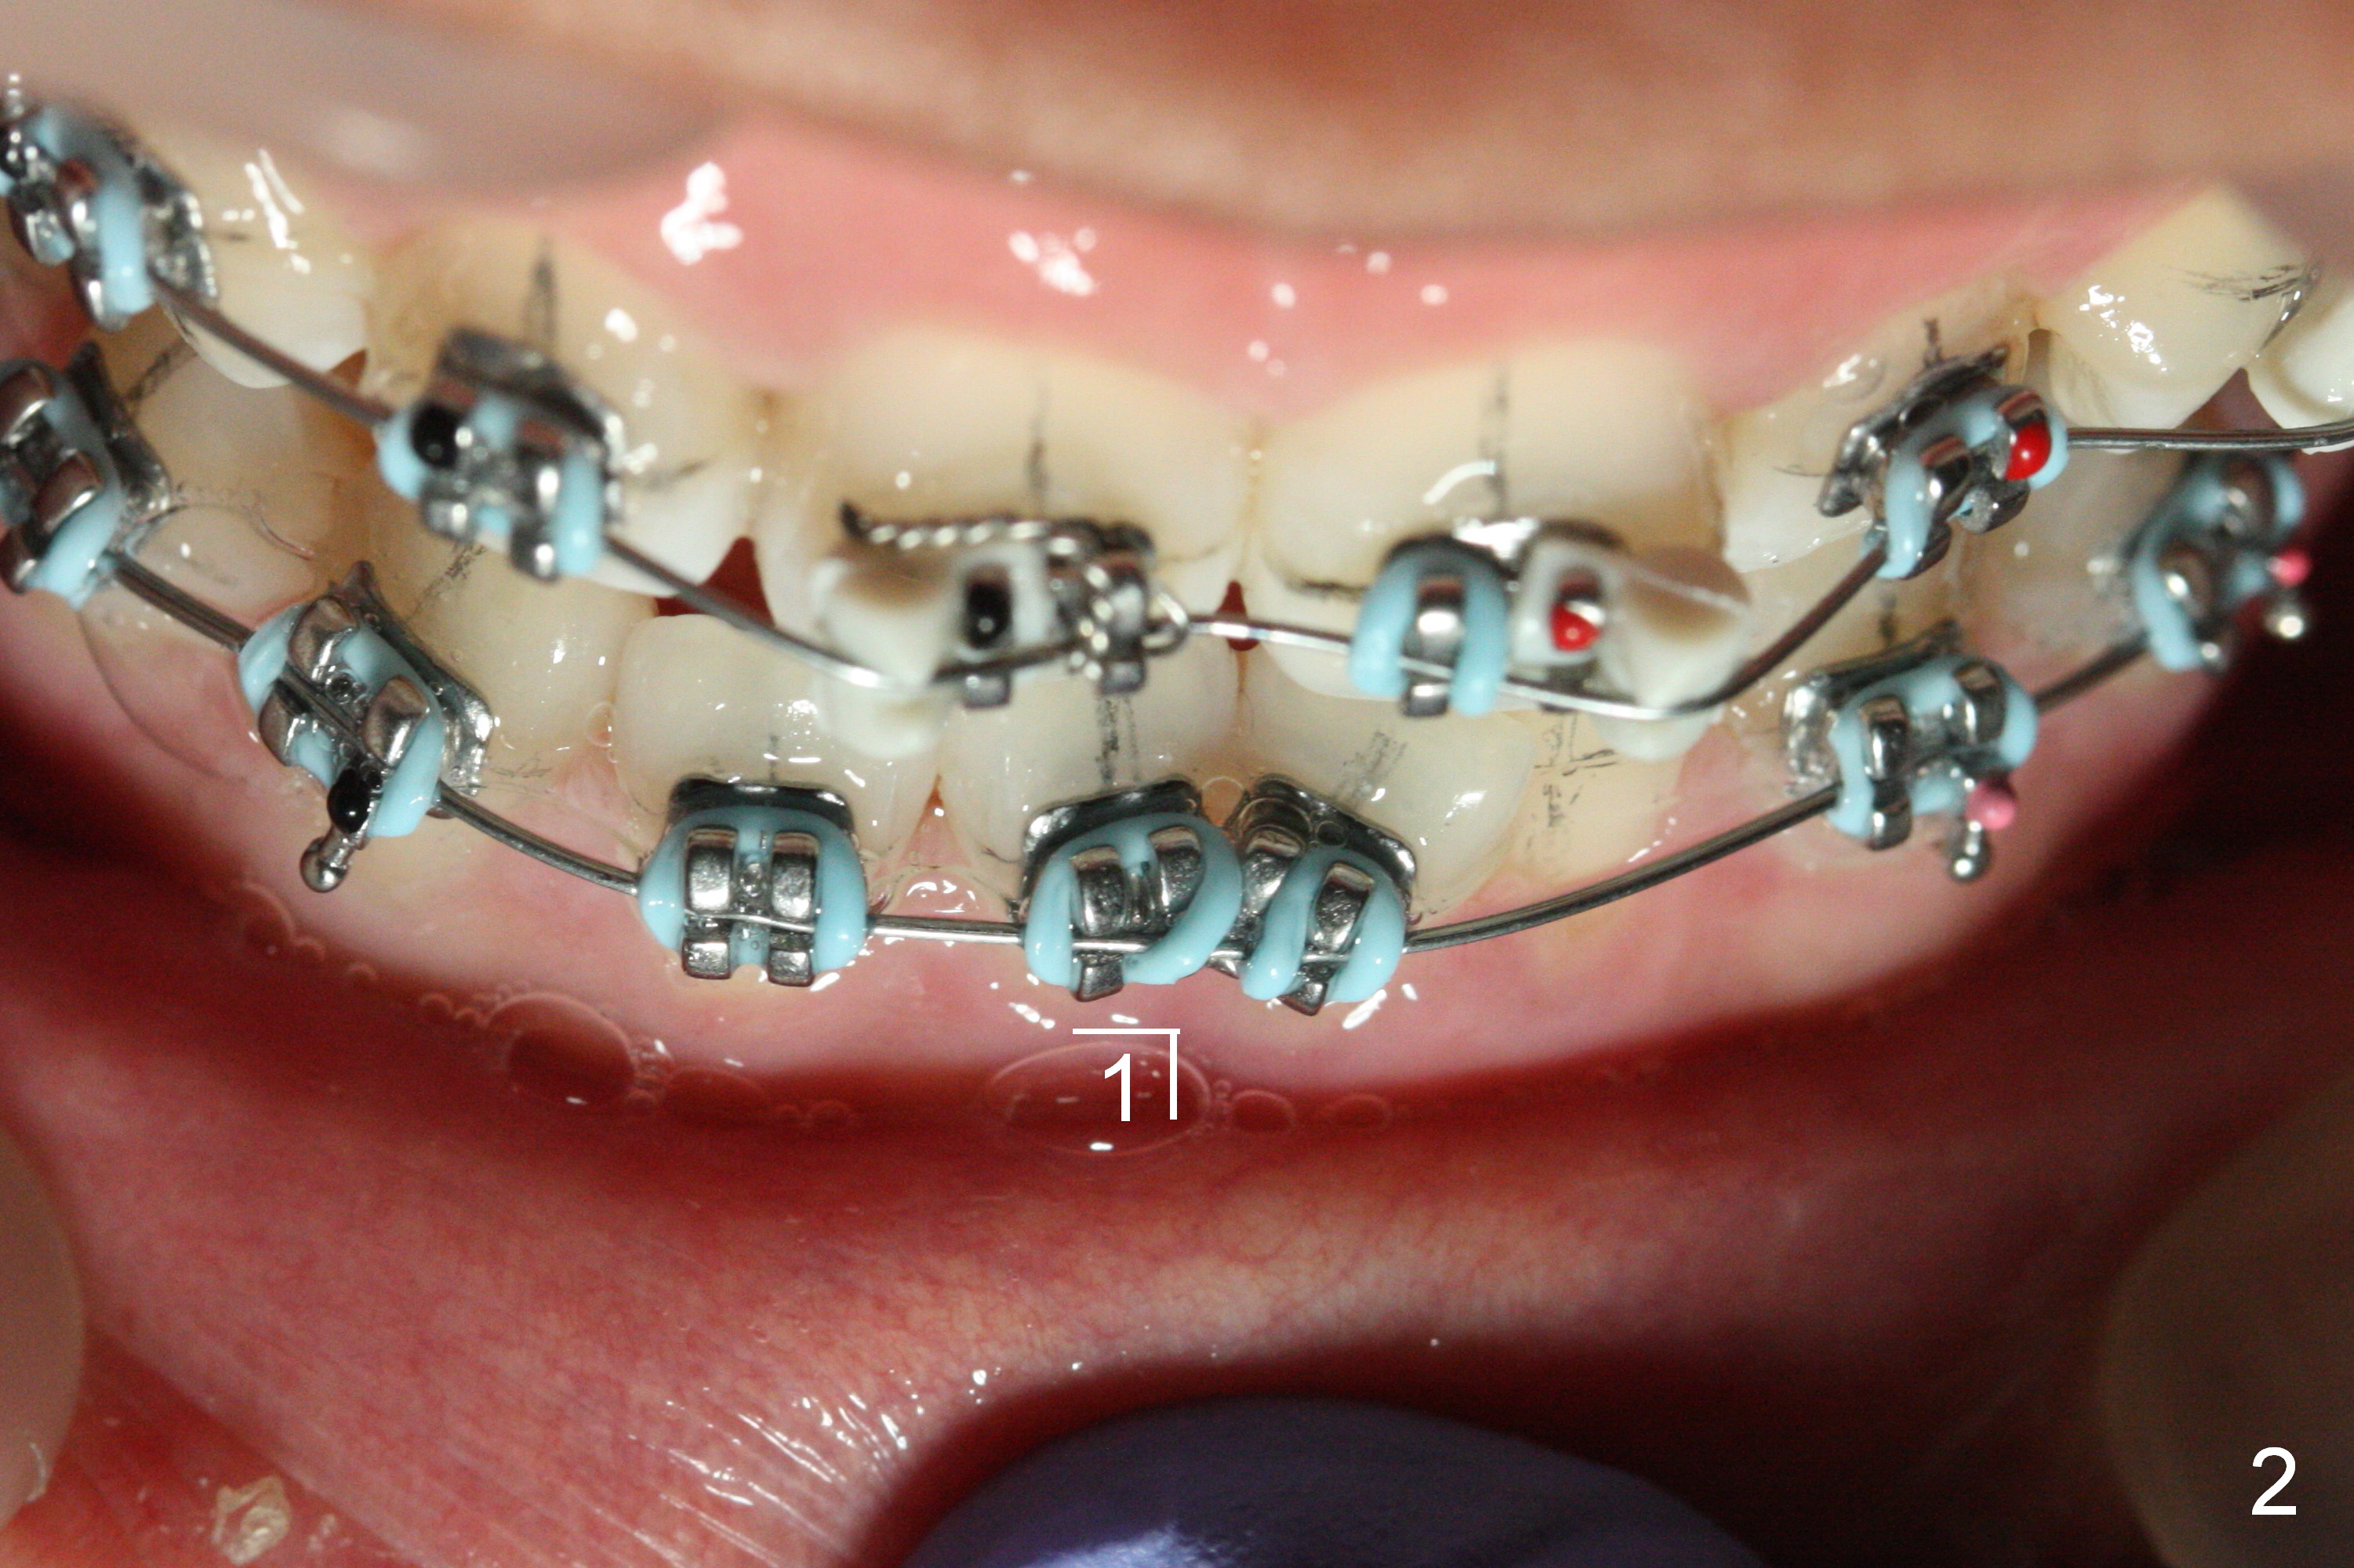

The second issue for this case is crowding of the lower incisor. There is no space between brackets LR 1 and LL 1 so that the alastiks at the sites are not fully engaged (Fig.2). Ideally the bracket at LL1 should be not placed initially. When there is severe crowding, lines for each bracket should be drawn. Brackets should be tried in without application of bonding material. What will happen in this region next appointment?